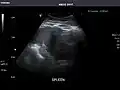

Abdominal Ultrasound (Full Exam)

STRUCTURED REPORT

(Technique: Transabdominal ultrasonography; Device: Toshiba Aplio XG)

Pancreas: Visualized portions unremarkable.

Spleen: Normal in size.

Ascites: None.

Aorta: Visualized portions normal in caliber, 16 x 15 mm.

IVC: Normal.

IMPRESSION:

Normal abdominal ultrasound.

Spleen -